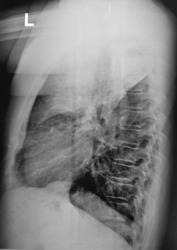

Контроль после флюорографии.  Жалоб нет!

Томограммы.

Возраст и предыдущая ФЛГ? А пока что саркома.

Спасибо! Пока останусь при своем мнении, такое поражение без клиники и без явного уменьшения объёма - саркома.

А объём, что сильно уменьшен, так по боковой, вроде бы и нет.

Саркома - потому что я не знаю иной патологии, такого размера поражения и без объёмного уменьшения. Тем более при отсутствии клиники: пневмония отпадает, остается саркома. Может, кто-то еще что предложит.

Жалоб нет или больной диссимулирует-всё одно. Ателектаз есть, нижнедолевой бронх сужен из вне,ФТБС-покажет, Нам остается только гадать.....

Ателектаз,а вот мне интересно почему верхушка воздушна или это  распад ?

Это не распад...А клапанные вздутия периферической ткани легкого-результат нарастающей обтурации бронха.